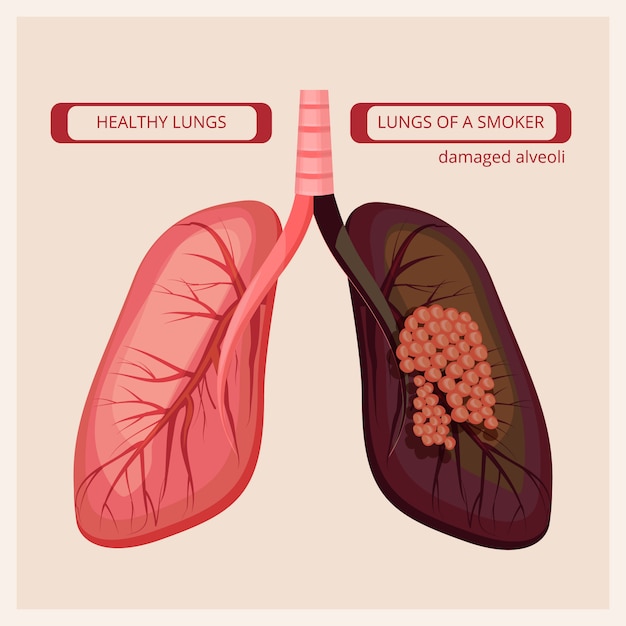

imagenes de pulmones sanos y enfermos

Posts: imagenes de pulmones sanos y enfermos